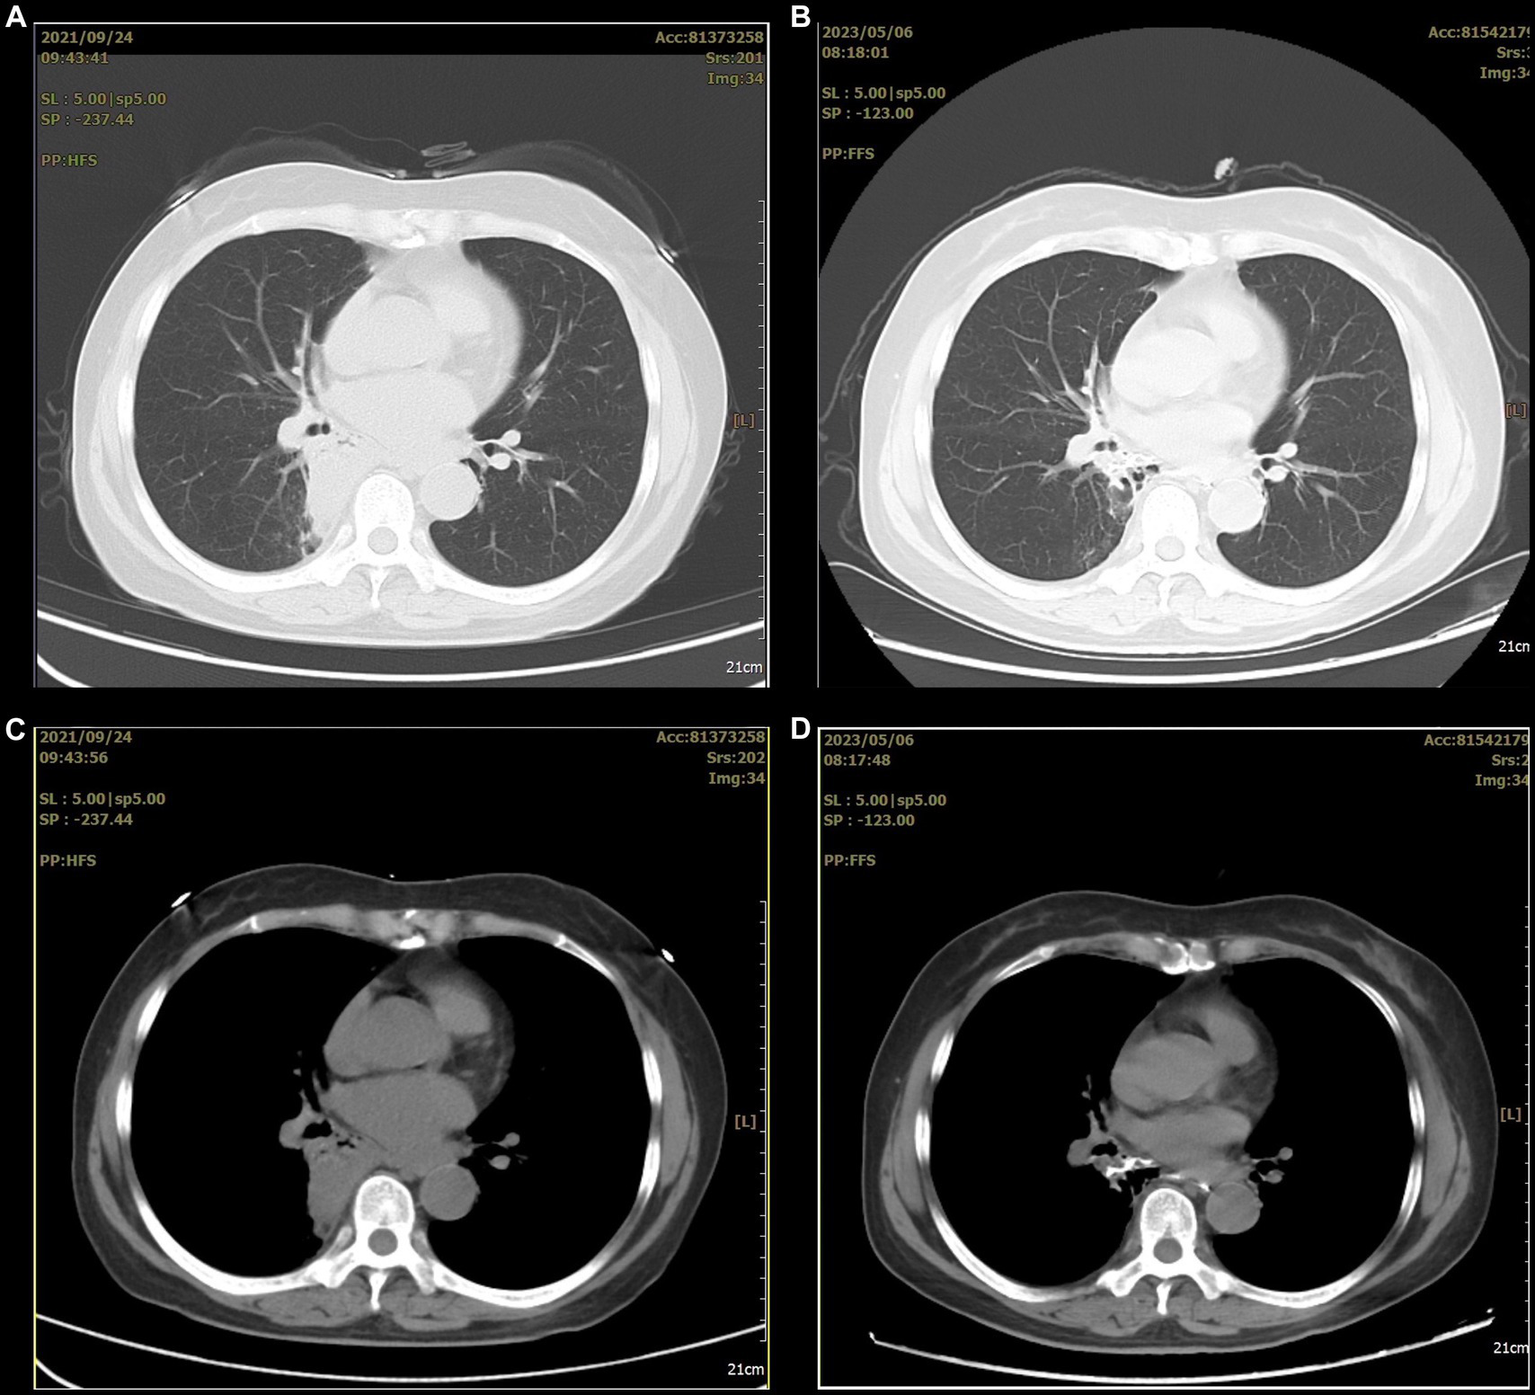

However, she refused surgical treatment due to fear of the risks associated with her advanced age and chose to be discharged. Therefore, we advised her to avoid a stimulating diet, especially alcohol. Assessed through telephone follow-up, the patient’s condition remained stable after discharge, but occasional coughing still occurred. Eighteen months later, a chest CT showed that the lesion had significantly decreased in size and showed local cystic changes (Figure 4). Therefore, we remain concerned that the patient’s condition may worsen in the future.

Figure 4

The before and after comparison of the arterial embolization treatment for the lesion. (A,C) A consolidation shadow can be seen in the right lung before the treatment. (B,D) After the treatment, the consolidation shadow appears significantly reduced.